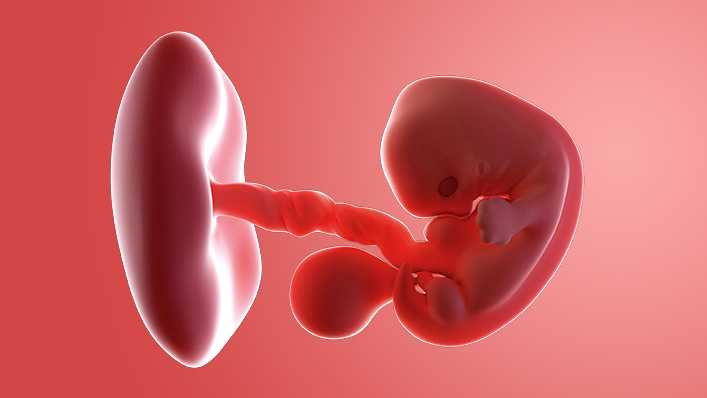

What does my baby look like?

Your baby, or embryo, is around 2mm long (about the size of a sesame seed).

The face is starting to take shape, with a tiny nose and little eyes, which stay closed until around 28 weeks. Your baby's brain and spinal cord are forming rapidly inside you.

Your baby already has some of its own blood vessels and a string of them will make up the umbilical cord. This cord delivers everything it needs from the placenta.

The placenta, which is being created now, will give your baby nutrients and oxygen, while removing waste products.